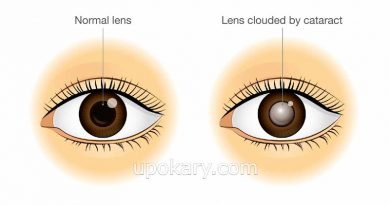

নিউমোনিয়া কী?

নিউমোনিয়া হল একটি ফুসফুসের সংক্রমণ যা ফুসফুসের অভ্যন্তরের ক্ষুদ্র শ্বাসনালীতে ব্যথা সৃষ্টি করে। শ্বাসনালীতে এত বেশি তরল জমে যায় যে নিঃশ্বাস নিতে কষ্ট হয়। নিউমোনিয়াতে শ্বাসকষ্ট, কাশি, জ্বর, বুকে ব্যথা, ঠান্ডা লাগা বা ক্লান্তি ইত্যাদি লক্ষণ দেখা দেয়।

করোনাভাইরাস ফুসফুসে কিভাবে ক্ষতি করে?

সাধারণত করোনভাইরাস ফুসফুসে তীব্র ব্যথা সৃষ্টি করে। কারণ, এটি ফুসফুসে শ্বাসনালীর মধ্যে থাকা কোষ এবং টিস্যুকে ক্ষতি করে। এই শ্বাসনালী হলো এমন জায়গা যেখানে আমাদের নিঃশ্বাসের সাথে নেওয়া অক্সিজেনকে প্রসেস করা হয়। এই প্রসেসকৃত অক্সিজেন পরে রক্তে সরবরাহ করা হয়।

ফুসফুসে শ্বাসনালীর মধ্যে থাকা কোষ এবং টিস্যুর ক্ষতির ফলে শ্বাসনালীগুলি আটকে যায়। শ্বাসনালীগুলি আটকে যাওয়ার বা জমাট বাঁধার কারণে তীব্র শ্বাসকষ্ট দেখা দেয়।